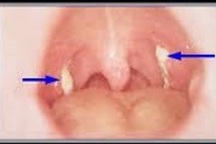

Người mắc bệnh bạch hầu thường xuất hiện những triệu chứng điển hình như sốt nhẹ, họng đỏ, nuốt đau, ho, khàn tiếng, mệt, da hơi xanh, chán ăn. Sau 2-3 ngày, người bệnh xuất hiện giả mạc mặt sau hoặc hai bên thành họng, có màu trắng ngà, xám hoặc đen. Giả mạc dai, dính, dễ chảy máu. Đây là dấu hiệu quan trọng nhất để phát hiện bệnh.

Ngoài ra, bệnh nhân có thể có dấu hiệu khó thở, nổi hạch ở dưới hàm làm sưng tấy vùng cổ. Nếu được phát hiện sớm, điều trị kịp thời người bệnh có thể hồi phục bình thường.